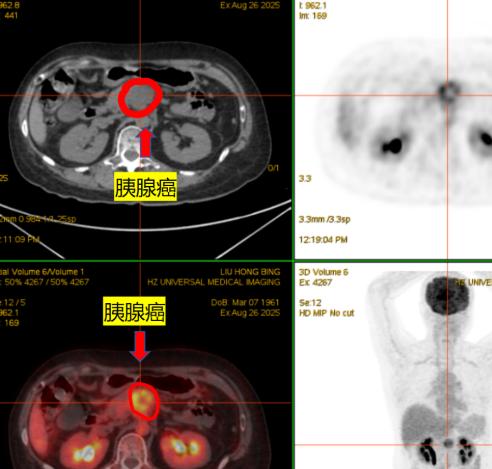

老谢的儿子民丰因为腹部疼痛剧烈被确诊为胰腺炎,孩子已经在ICU住了整整四天了,这四天老谢没黑没白的在外面守着却一面也见不着孩子。

我孩子的爷爷是胰腺癌,从发病到人走就半年人就走了,这种病很疼的,我看到有个好心的网友给民丰的爸爸发私信说,让他尽快联系一下北京刘鲁明教授说刘教授是只看胰腺的其他的病不看,真的希望这条消息能给他们带来新的希望,好希望能有奇迹发生在他们身上能留下这个可怜的孩子!